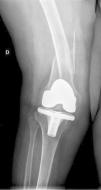

The interprosthetic fractures occurred between 2 and 8 months after the hip surgery, all of them were low-energy produced. In four cases they were located at diaphyseal level and in three at supracondylar level, two with ultracongruent and one with posterior stabilised polyethylene. In all cases both implants were stable and not affected by the fracture line. In two cases the fracture line affected the distal cement plug of the hip arthroplasty (Fig. 1). Following Platzer's classification, the fractures were 4 type IA, and 3 type IIA adjacent to the knee arthroplasties (Figs. 3 and 4). Four patients were assessed with a Singh index of 3 and 3 with an index of 4.

All of the patients walked with the aid of orthopaedic devices prior to the fracture, 3 with a walking frame and 4 with crutches. Union took place in all cases with a mean of 4.5 months,4–7 two of them had diaphyseal fractures with delayed union. There were no angles in union greater than 5°, no reoperations or complications or evolutionary complications presented, even in one patient with a short plate which only overlapped 3cm who made satisfactory progress (Fig. 2). All the patients regained their walking ability prior to the fracture except for one female patient who was lost to follow-up at 6 months, the fracture having healed. Clinically, the three patients with a supracondylar fracture lost a mean of 20° knee flexion, previous hip mobility was not altered in any of the patients.